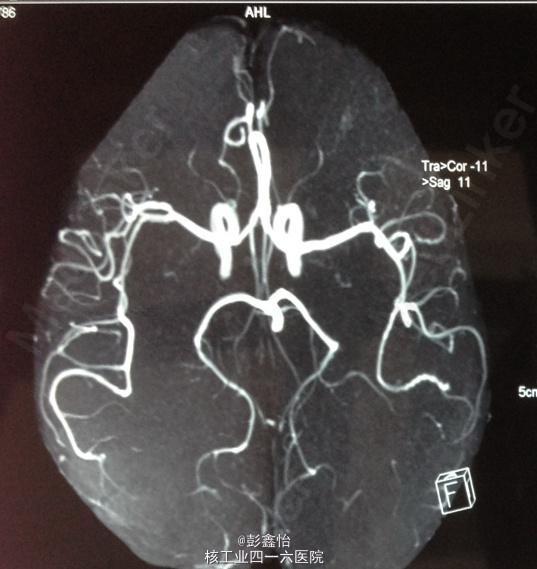

PE: NE:神经专科查体均正常; ABCD2评分为3分 NIHSS评分为0分; 入院后辅助检查均正常,CT、MRI+MRA、脑电图、视频脑电监测均未见异常。

因患者无明显肢体抽搐及局部泛化过程,脑电监测正常,基本可除外癫痫发作。诊断TIA,予以阿司匹林、他汀降脂等治疗,但TIA继续发作。 追加血管评估,但TCD、DSA、颈部血管超声均未发现异常,在原有治疗基础上,予以双抗、改善循环、营养神经加强治疗 但患者仍频繁发作TIA,3天内共发作20余次。判断为治疗抵抗,继续加用抗凝、脑保护,最后加用羟乙基淀粉扩容治疗后发作终止,但患者出现右侧肢体轻偏瘫。 复查DWI:左侧基底节区出现急性梗死灶; 复查MRA、DSA均未见异常。